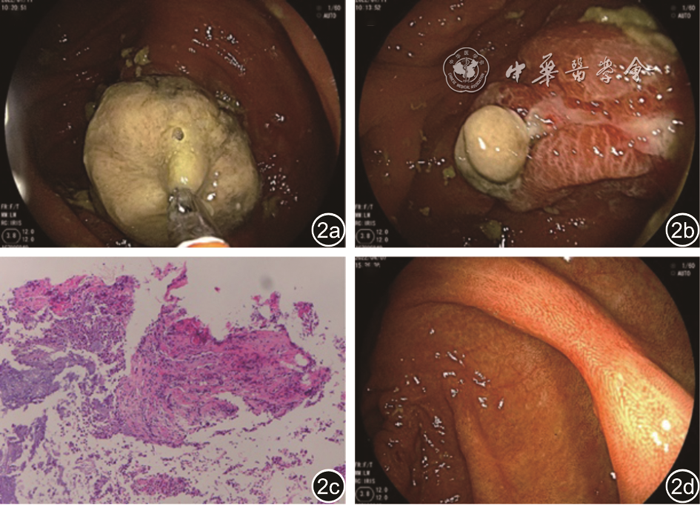

图1 患者腹盆部CT检查。图a、b:箭头所见回肠末端套入升结肠;图c、d治疗后复查已好转